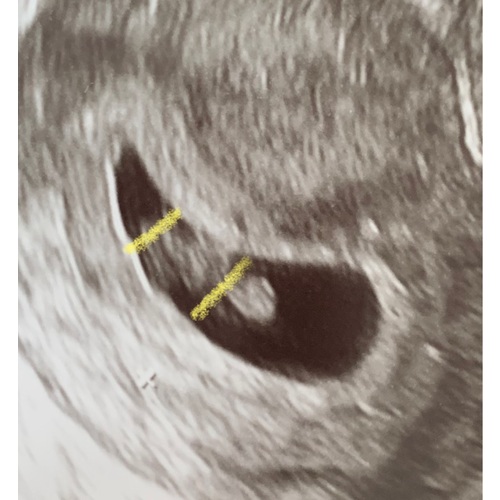

Oke dan ben ik heel erg benieuwd wat dit dan eventueel kan zijn volgens de ramzi methode dit is een inwendige echo geweest bij 8 weken zwangerschap